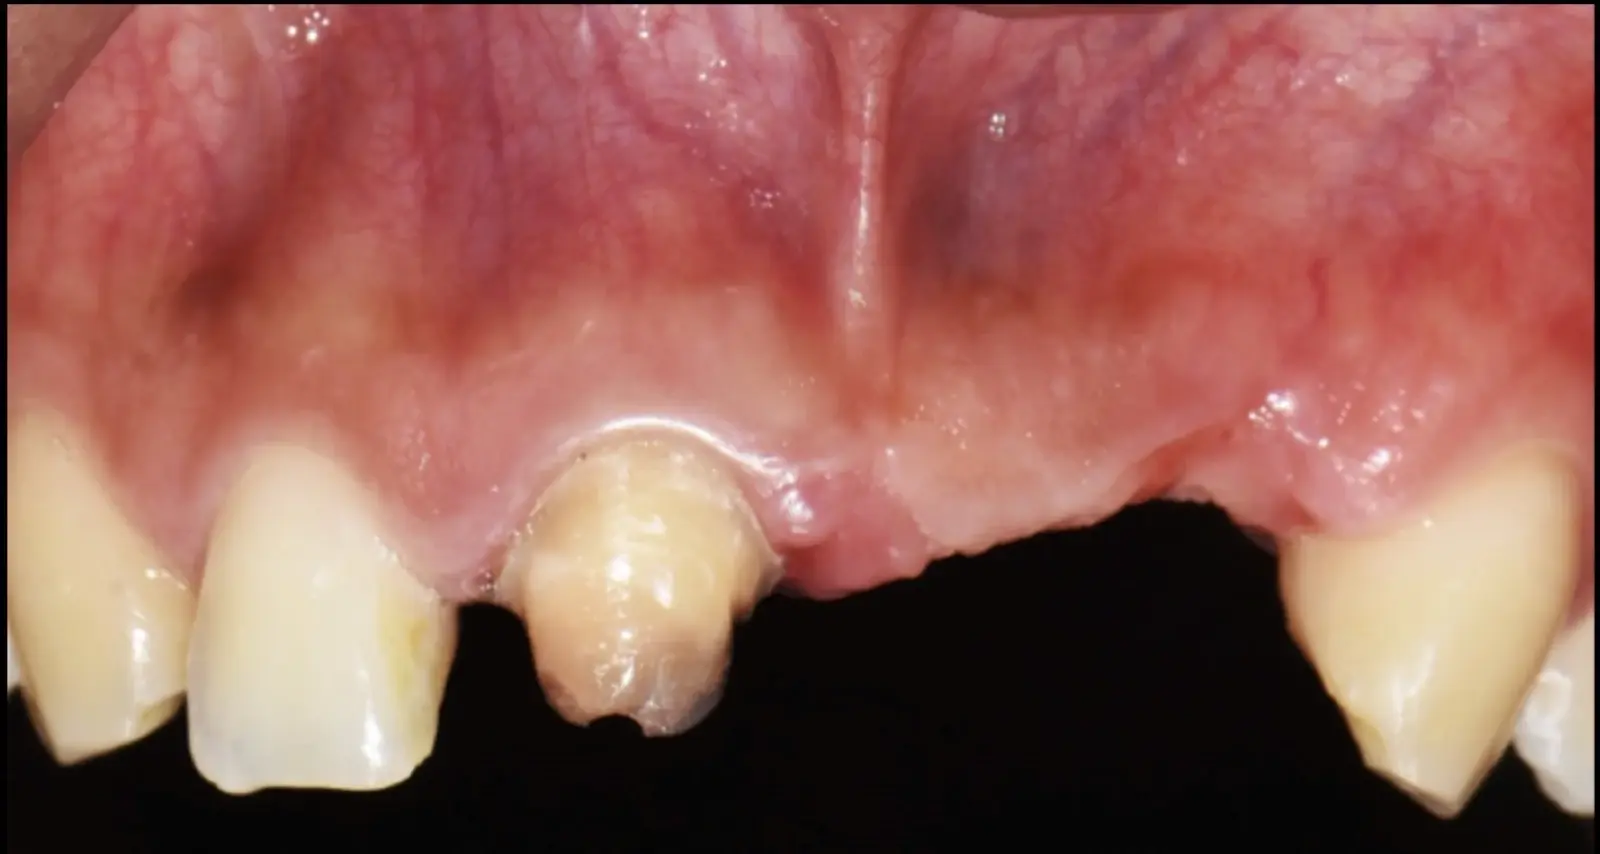

Figura 45. Afrontamiento de colgajo y sutura (a - e). Control a los 7 días postquirúrgico (f).

Figura 46. Control a los 10 días post cirugía.